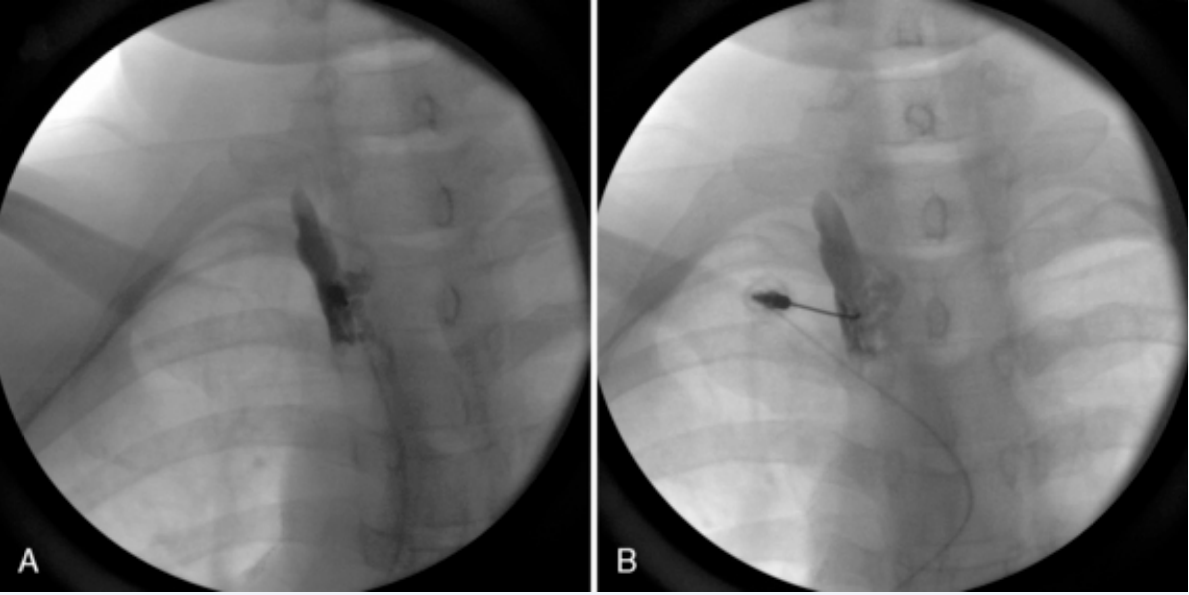

Selective thoracic nerve root blocks (STNRBs) are helpful procedures [24] (Figure 2).

Shows a single level thoracic nerve root injection (also  known as a transforminal epidural injection).

Figure 2: Shows a single level thoracic nerve root injection (also known as a transforminal epidural injection).

The most common indication is where there is radiculopathy and ICNBs have not relieved the symptoms. If an MRI scan has not being completed then it is useful to eliminate underlying red flags such as a vertebral facture / collapse, disc herniation, entrapment of the nerve root, metastatic disease or infection in advance of the procedure.

When steroids are added to the local anaesthetic, the goal is to generate a long-term pain relief, mostly in patients with radiculopathy symptoms. After a successful STNRB (i.e. 50% reduction in pain), it is recommended to go on with pulsed radiofrequency of DRG for a definite pain relief. Thoracic DRG radiofrequency is difficult because of being located anteriority in the intervertebral foramen [23].

The anatomical location of the foraminal arteries is variable; the study by Kroszczynski et al. [26], found that at thoracolumbar levels, the artery is almost always (92% ± 5%) located anterosuperior to the nerve. At typical thoracic levels is less often anterosuperior (38% ± 19%), but more often anterior to the nerve. It is known that the location of the Adamkiewicz artery is very irregular, which makes even more dangerous the possibility of secondary spinal cord injury and paraplegia as this is the main blood supply of the thoracolumbar spinal cord. It is noteworthy to mention that the foraminal arteries supply the spinal cord, so the intra-arterial injection is very dangerous [27,28]